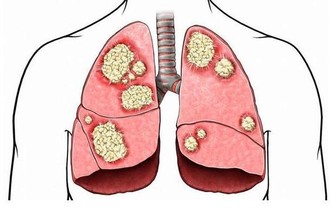

經常久坐不動,還會降低人體的胃腸動力,減少消化液的分泌,這不利於人體對食物的消化吸收,容易出現食慾不振、消化不良、腹脹、便秘等現象,可能會引起胃潰瘍、十二指腸潰瘍等疾病,嚴重的還會導致結腸癌。